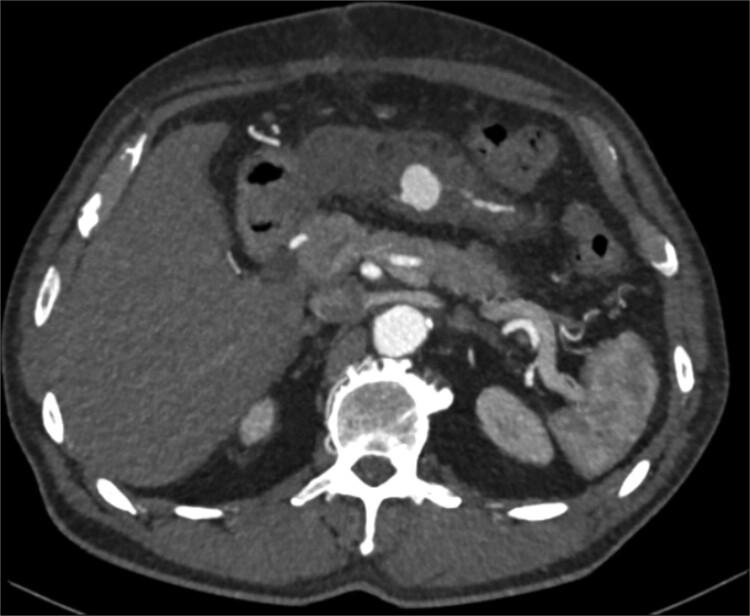

We present the first published account of a pseudoaneurysm of the Marginal artery of Drummond (MAoD) following an emergency open surgical repair of an inflammatory abdominal aortic aneurysm, in which the inferior mesenteric artery was ligated. This was hypothesized to be an iatrogenic injury secondary to retraction of the colonic mesentery during dissection of the aneurysm neck. The risk of pseudoaneurysm growth and rupture versus bowel ischaemia were evaluated in the post-operative phase. Ultimately, the patient underwent successful interventional embolization of the MAoD with no signs of bowel ischaemia post-intervention.

我们首次发表了关于在紧急开放性手术修复炎症性腹主动脉瘤并结扎肠系膜下动脉后,发生的德拉蒙德边缘动脉(MAoD)假性动脉瘤的病例报告。据推测,这是由于在动脉瘤颈部解剖过程中结肠系膜回缩导致的医源性损伤。在术后阶段评估了假性动脉瘤生长和破裂与肠缺血的风险。最终,患者成功接受了MAoD介入栓塞治疗,术后无肠缺血迹象。